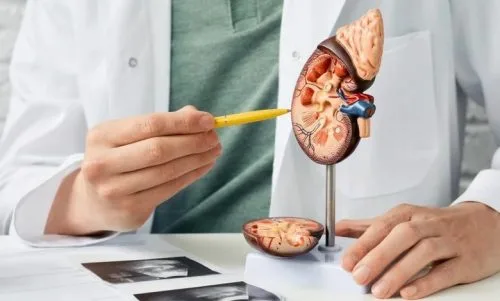

- نفروپاتی دیابتی

- تنگی عروق کلیه